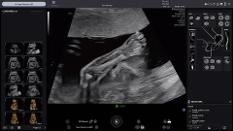

- Précision accrue : Son imagerie plus puissante vous aide à poser des diagnostics surs même avec des patientes difficiles

- Efficacité : Ses outils d’intelligence artificielle peuvent réduire jusqu’à 65 %* le nombre de clics nécessaires pour réaliser les examens standard du deuxième trimestre.

Sa philosophie est différente… Offrir plus de marge de manœuvre, tout en conservant une ergonomie accessible et une qualité d’image élevée.